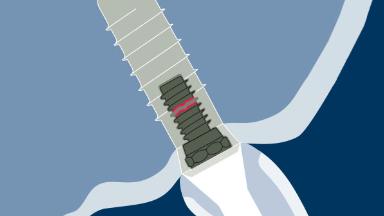

种植治疗已被证明是一种成功的治疗方式,它适用于广泛的牙齿修复临床适应症。虽然如此,但还是会出现并发症,有确凿的证据表明牙种植体的修复并发症发生率比天然牙齿高。这些并发症通常被称为“硬件并发症”,务必要了解它们的起因和最佳处理方式。本模块将对固定修复体的种植硬件并发症进行分类,然后根据分类阐明其不同的起因、最佳预防方法和处理方法。